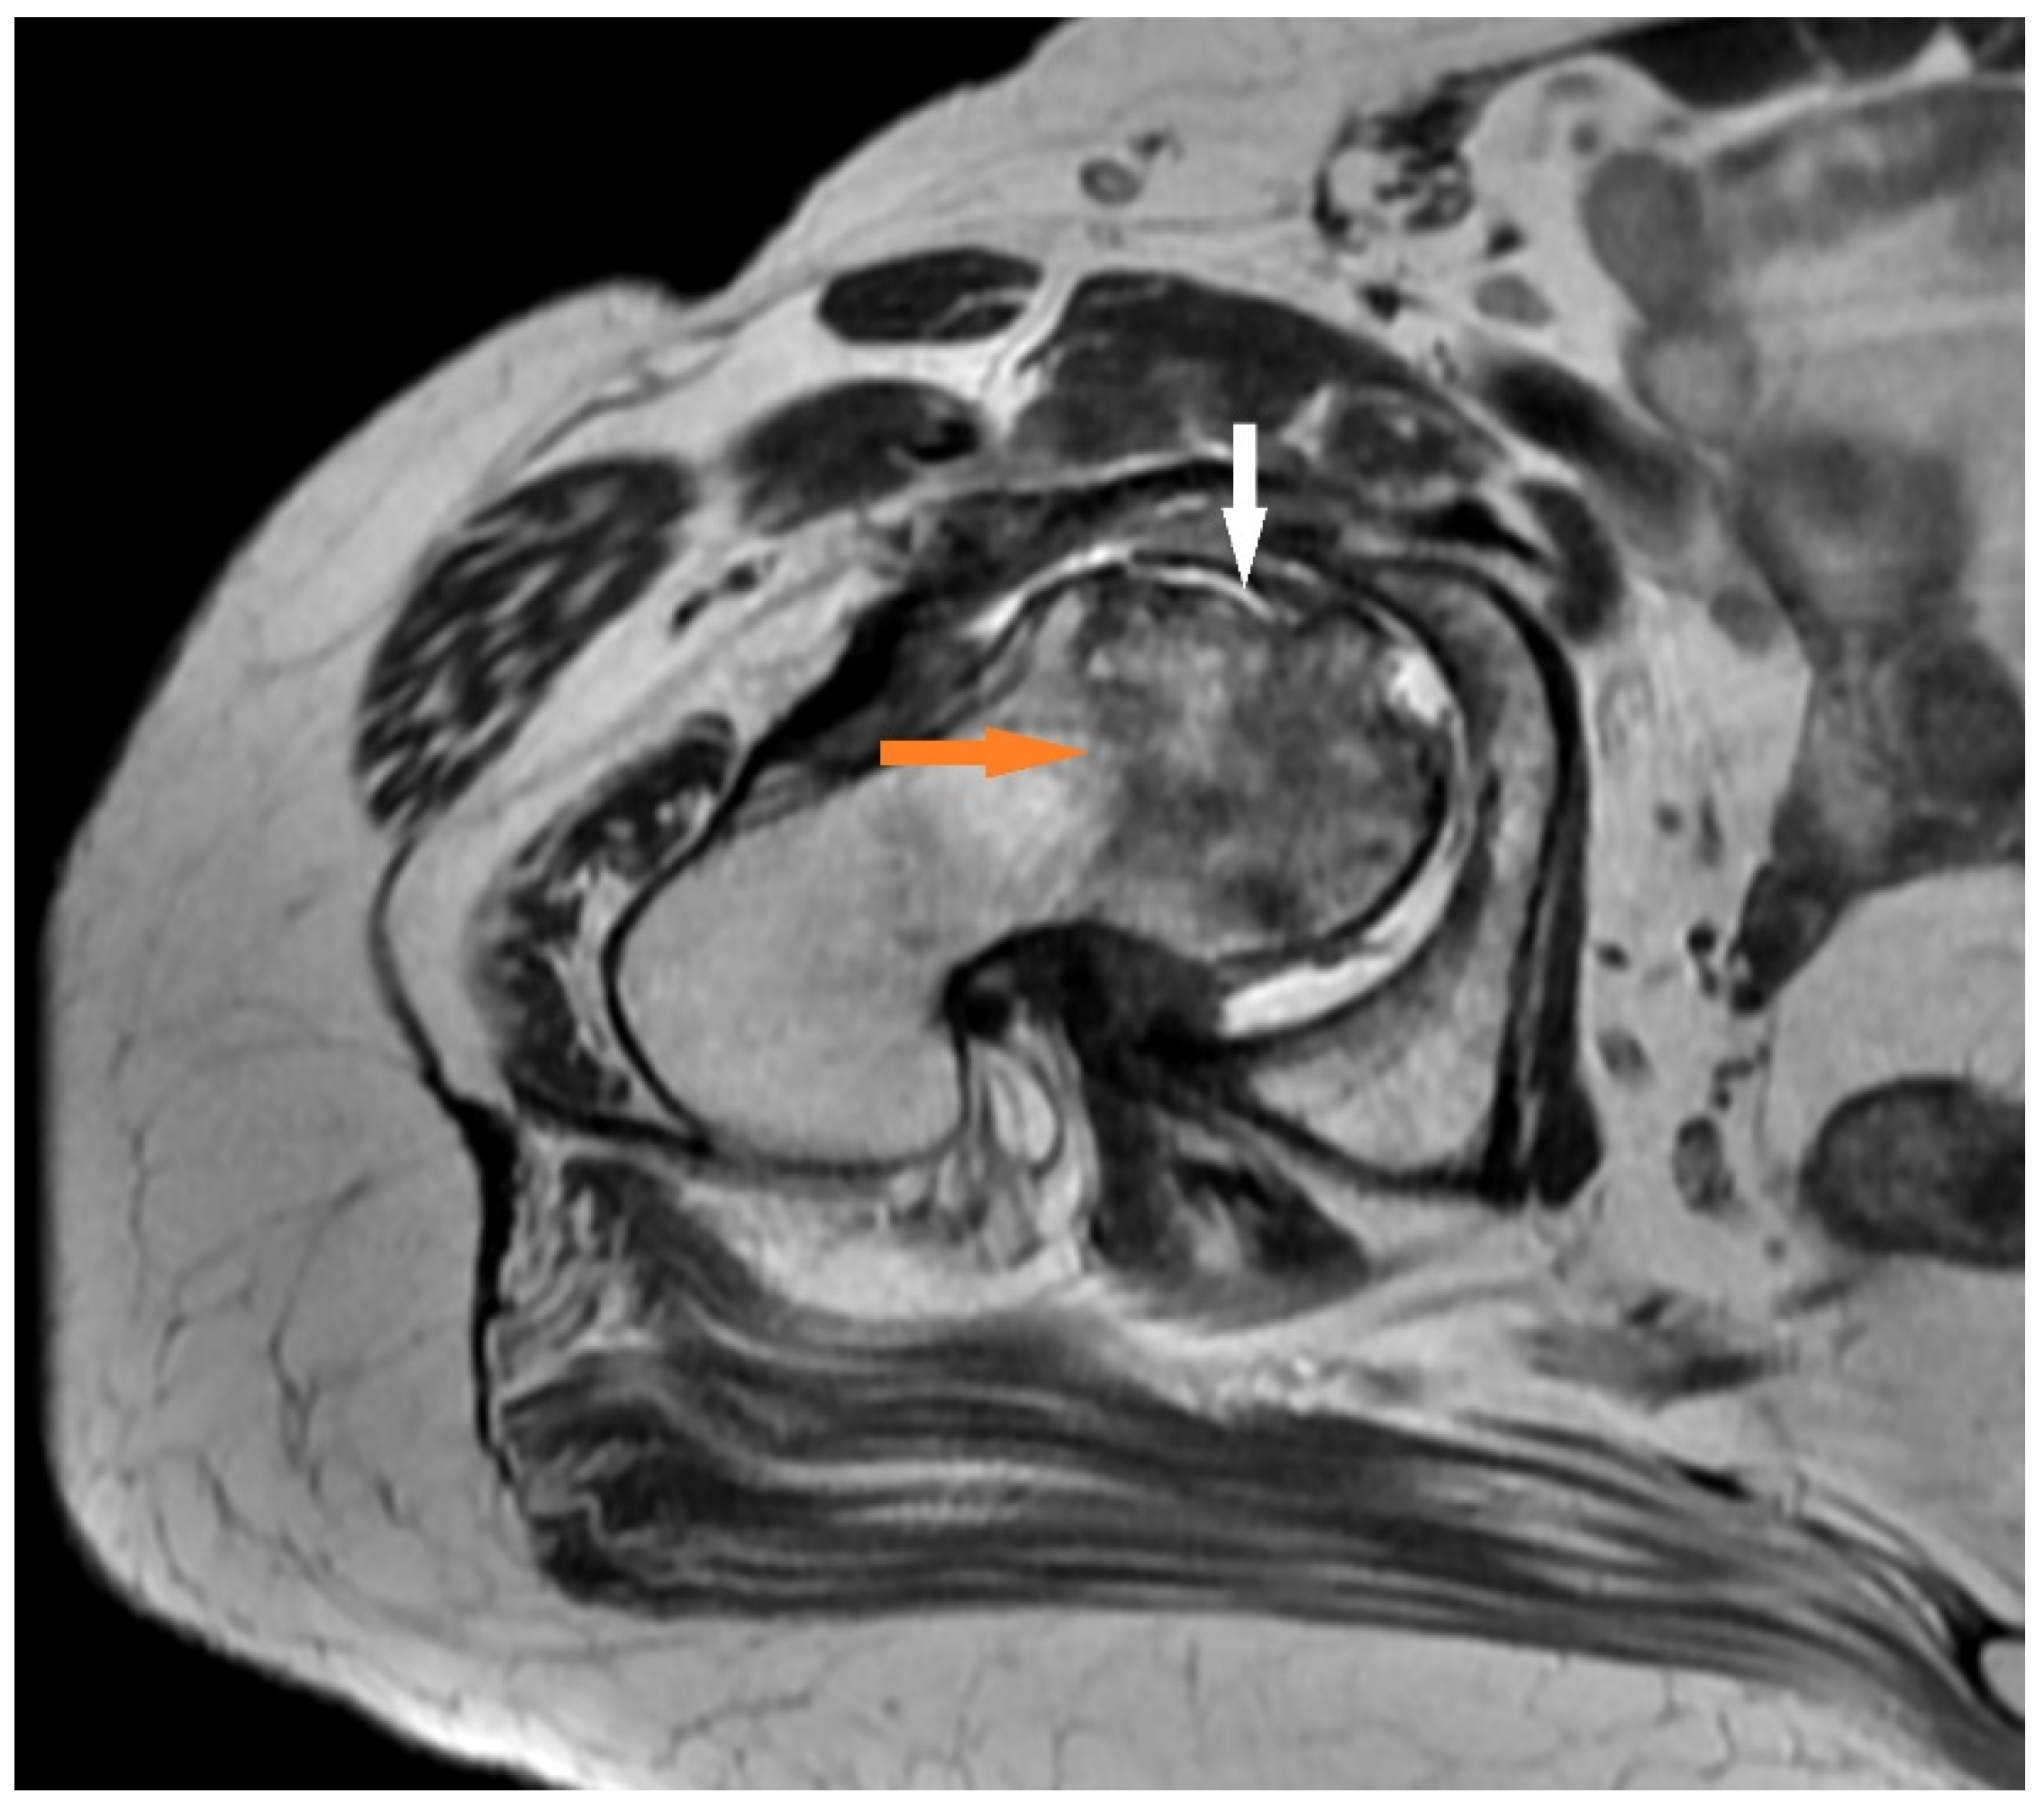

- T2 FR FSE: This may show a second hyperintense inner line between normal marrow and ischemic marrow. This appearance is highly specific for AVN of the hip and is known as the “double line sign”.

3.1.1. Case 1 (Patient No. 5)